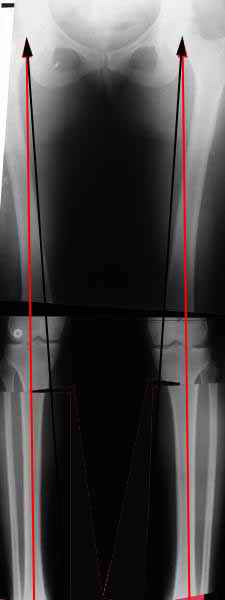

Вот, с учетом и без учета, и на разных уровнях...

AC> Вот, с учетом и без учета, и на разных уровнях...

AC> Саша Артемьев, может, для данного случая свой вариант нарисуешь?

Из приведнной схемы не совсеим понял что означают разноцветные линии.

И зачем латерализация периферического фрагмента. Я всегда делаю медиализацию. См схему. И для данного случая медиализация подходит как нельзя лучше.

a> Из приведнной схемы не совсеим понял что означают разноцветные линии.

Черные - это нынешняя механическая ось. Красные - это планируемая правильная ось.

a> И зачем латерализация периферического фрагмента.

;-) Читайте Палея. Стр. 114-115.

a> Я всегда делаю медиализацию. См схему. И для данного случая

Медиализация - это чисто эстетический прием, как я понимаю. Поскольку если делать остеотомию ниже вершины деформации, для восстановления оси надо делать смещение по ширине, в данном случае как раз латерализацию.

А вот на схемке без осей - там на разных уровнях (который правильнее?) устранение варуса чисто открытым клином без медиализации-латерализации. Если как-то так сделать - этого недостаточно будет?